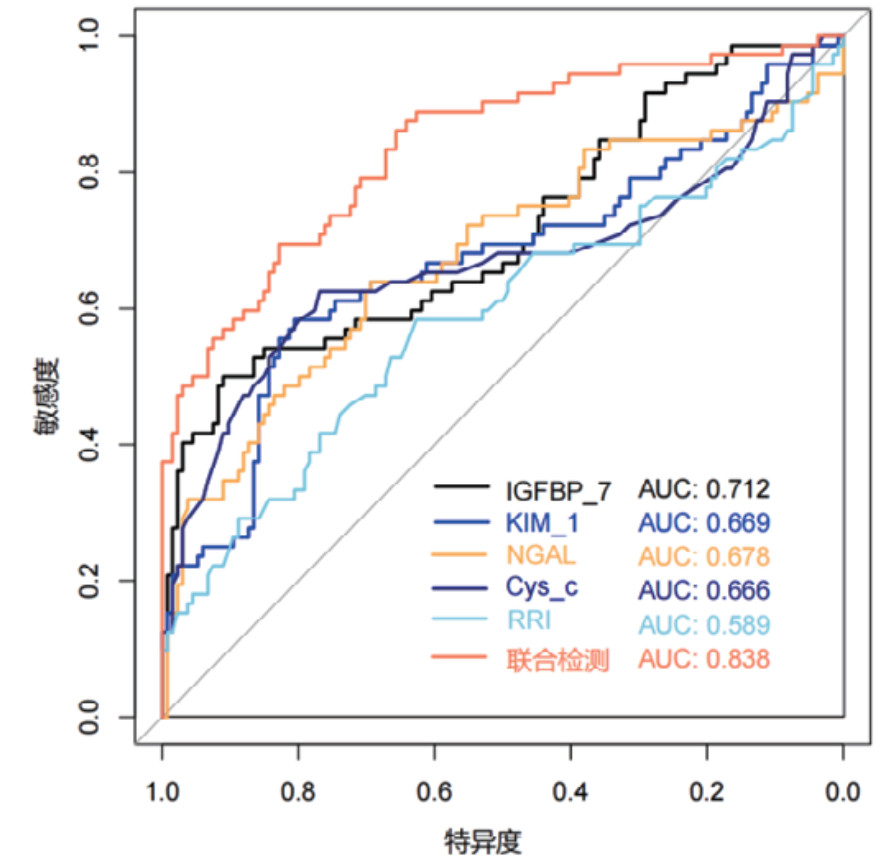

对各时间段血清Cys-C、IGFBP-7、KIM-1、NGAL和超声RRI水平及联合检测进行ROC曲线绘制,计算不同时间段联合检测的AUC值、最佳截断值、敏感度、特异度和约登指数。结果显示,联合检测0 h、12 h、24 h和48 h的AUC值分别为0.838(95%CI: 0.778~0.897)、0.852(95%CI: 0.797~0.907)、0.868(95%CI: 0.816~0.921)和0.872(95%CI: 0.820~0.924),见表 3。不同时段的AUC值提示联合检测的诊断效能要高于单项指标检测,结果见图 2、图 3、图 4和图 5。各指标各时间段的详细回归系数、标准误、P值、比值比(OR)及其95%置信区间见补充表S1。

| 检测变量 | AUC | 95%CI | 截断值 | 敏感度 | 特异度 | 约登指数 |

| 联合检测(0 h) | 0.838 | 0.778~0.897 | 0.403 | 69.44% | 82.83% | 0.523 |

| 联合检测(12 h) | 0.852 | 0.797~0.907 | 0.316 | 79.17% | 79.10% | 0.583 |

| 联合检测(24 h) | 0.868 | 0.816~0.921 | 0.309 | 81.94% | 80.60% | 0.625 |

| 联合检测(48 h) | 0.872 | 0.820~0.924 | 0.272 | 84.72% | 78.36% | 0.631 |

|

| 图 2 单项和联合检测0 h的ROC曲线 |

|

|

|

本研究结果显示,既往存在肾脏疾病是发生AKI的危险因素,AKI患者早期SCr和BUN水平显著高于非AKI组患者,AKI组患者的eGFR指标更低。其次,AKI组患者在0 h、12 h、24 h和48 h时间段内,血清NGAL、Cys-C、KIM-1、IGFBP-7水平及超声RRI值均高于非AKI组更高。这一结果提示,该生物标志物和RRI值的变化可以作为AKI早期诊断的敏感指标。此外,RRI值的升高也反映了肾脏血管阻力的增加和肾脏血流灌注的减少,是AKI发生的重要预测因素。但是单一指标的检测存在局限性,各项指标绘制的ROC曲线AUC值相对偏低,联合检测的AUC值优于各单项指标检测,其中联合检测48 h的AUC值最高为0.872(95%CI: 0.820~0.924),且敏感度和特异度相对较高。对各时间段联合检测指标显示各时间段预测性能比较接近,AUC值均大于0.8,提示联合检测稳定性和预测性能良好。此外,对各指标随时间变化的动态监测显示,Cys-C和KIM-1呈持续上升趋势,IGFBP-7在12 h达峰值后略有下降,NGAL在早期即显著升高并维持高水平,RRI随时间推移逐渐上升。这些指标的动态监测为AKI的早期识别、严重程度评估和预后判断提供了重要依据。不同指标在时间维度上的变化特征也反映了AKI发生发展过程中不同的病理生理机制。